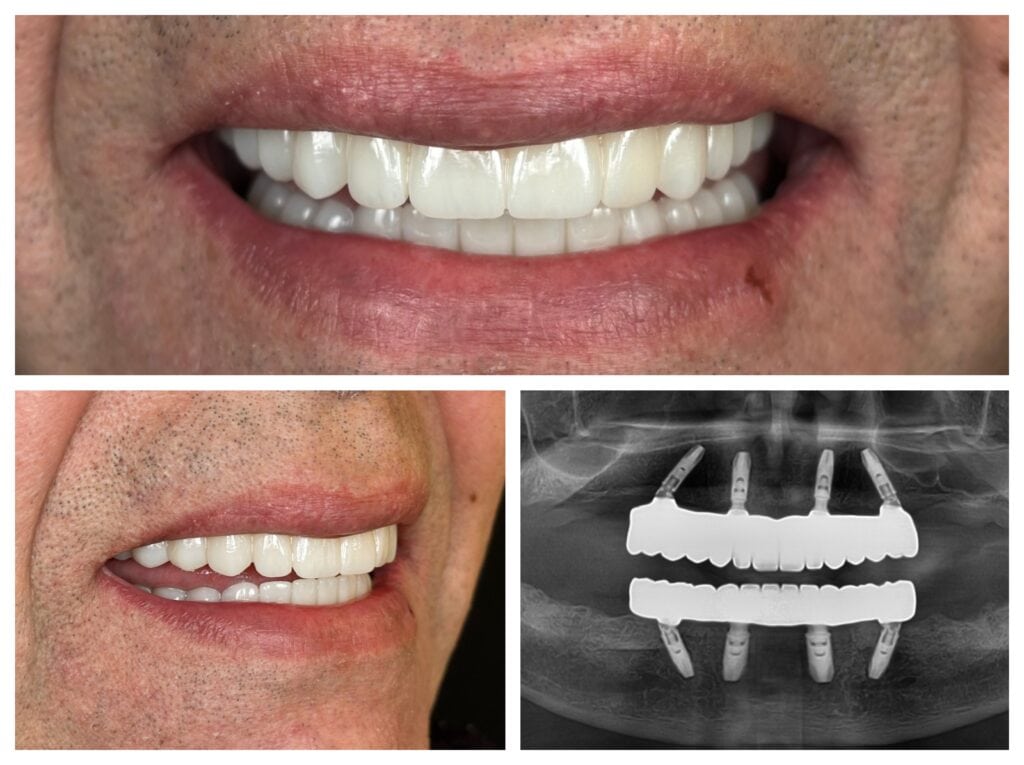

The Final Result: Zirconia All-on-4 Fixed Prosthesis with Smile Design

During the 4-month healing period, the implants fully integrated with the bone (osseointegration). Then came the “artistic” part of the process.

Digital Smile Design and Mock-up

We didn’t just create teeth; we created harmony. We took the patient’s facial characteristics and lip line into account. Before the final prosthesis, we created a 3D printed plastic trial (mock-up) to check the bite and aesthetics. We only proceeded to final production once everything was perfect.

Monolithic Zirconia and Custom Ceramic Gum

The material for the final bridge was monolithic zirconia, currently one of the most durable and aesthetic dental materials available. For a natural effect, we complemented the restoration with custom ceramic artificial gums, which restored the fullness of the face and masked the signs of previous bone loss.

Monolithic zirconia All-on-4 prosthesis with custom ceramic artificial gum

Zirconia All-on-4 fixed restoration